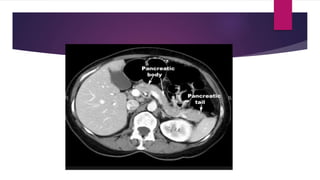

 CT: Not necessary if only a mild attack

 CT advised when

 Diagnostic uncertainty

 Severe acute pancreatitis to diff from interstitial and necrotizing

pancreatitis

 Patients with MODS and progressive sepsis

 Localized complication is suspected

 CT: Notnecessary if only a mild attack  CT advised when  Diagnostic uncertainty  Severe acute pancreatitis to diff from interstitial and necrotizing pancreatitis  Patients with MODS and progressive sepsis  Localized complication is suspected